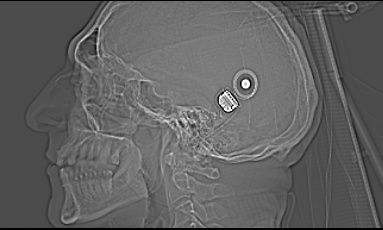

Mit einem Pflaster über der Wunde konnte ich bereits wieder nach Hause. Mit auf den Weg bekam ich ein Computertomogramm meines Schädels. Und nun sah ich es schwarz auf weiss: das Implantat ist gesetzt.